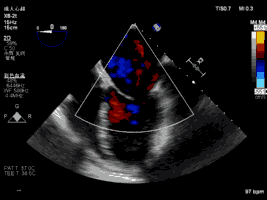

夹合术前:彩色多普勒示重度二尖瓣反流

夹合术后:彩色多普勒示轻微二尖瓣反流